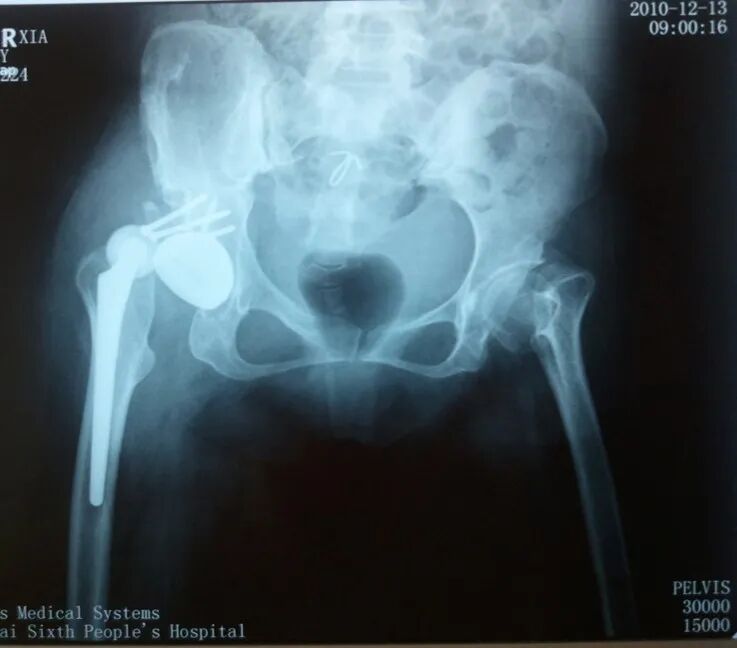

术后5天,脱位

术后4月,再一次脱位

屋漏偏遭连夜雨